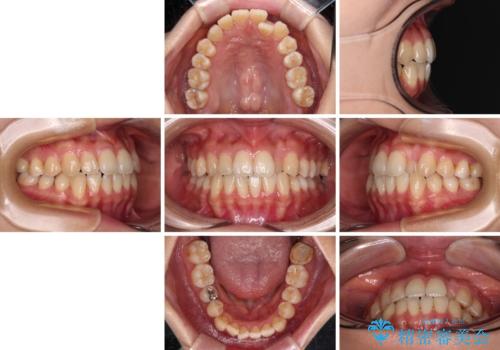

クロスバイトの前歯を改善 ワイヤー装置で楽々矯正治療

- 前歯のクロスバイトを改善したいとのことで来院された患者様です。

マウスピース矯正は自己管理が煩わしいとのことで、ワイヤー装置による矯正治療を行うこととしました。

舌の突出癖が認められたため、デコボコ改善に伴い前歯が前突する可能性があったため、舌のトレーニングをしっかりと行うよう指導しながら治療を進めることとしました。

左下の奥歯は根管治療後に放置されていたため、咬み合わせを調整しながら矯正治療を行い、最後にオールセラミッククラウンにて補綴治療を行うこととしました。

舌のトレーニングをしっかりと行っていただき、補綴治療も含めて1年強の短期間で治療を終えることができました。